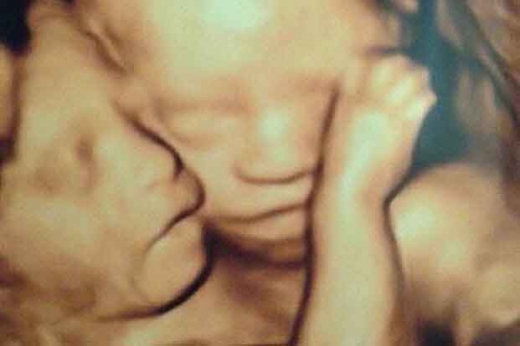

사진 : 생존한 사라의 모습과 출생 당시 가슴이 붙어 있던 쌍둥이 모습 (해당 페이스북 캡처)

출산 전 초음파 검사 등으로 쌍둥이가 붙어 있다는 사실을 알아낸 의료진은 심혈을 기울여 수술에 임했지만, 심장 쪽의 과다 출혈로 인해 올리비아는 끝내 생존할 수 없었고 사라라고 이름이 지어진 딸만 생존하게 할 수 있었다고 밝혔다.

지난 5일, 쌍둥이의 어머니인 앰버는 생존한 사라의 모습을 처음으로 자신의 페이스북에 올리며 "비록 딸 한 명은 잃었지만, 나머지는 잃을 수가 없었다"며 "나의 귀여운 젖먹이 딸"이라는 글을 올려 네티즌들을 슬픈 감동에 젖게 했다.